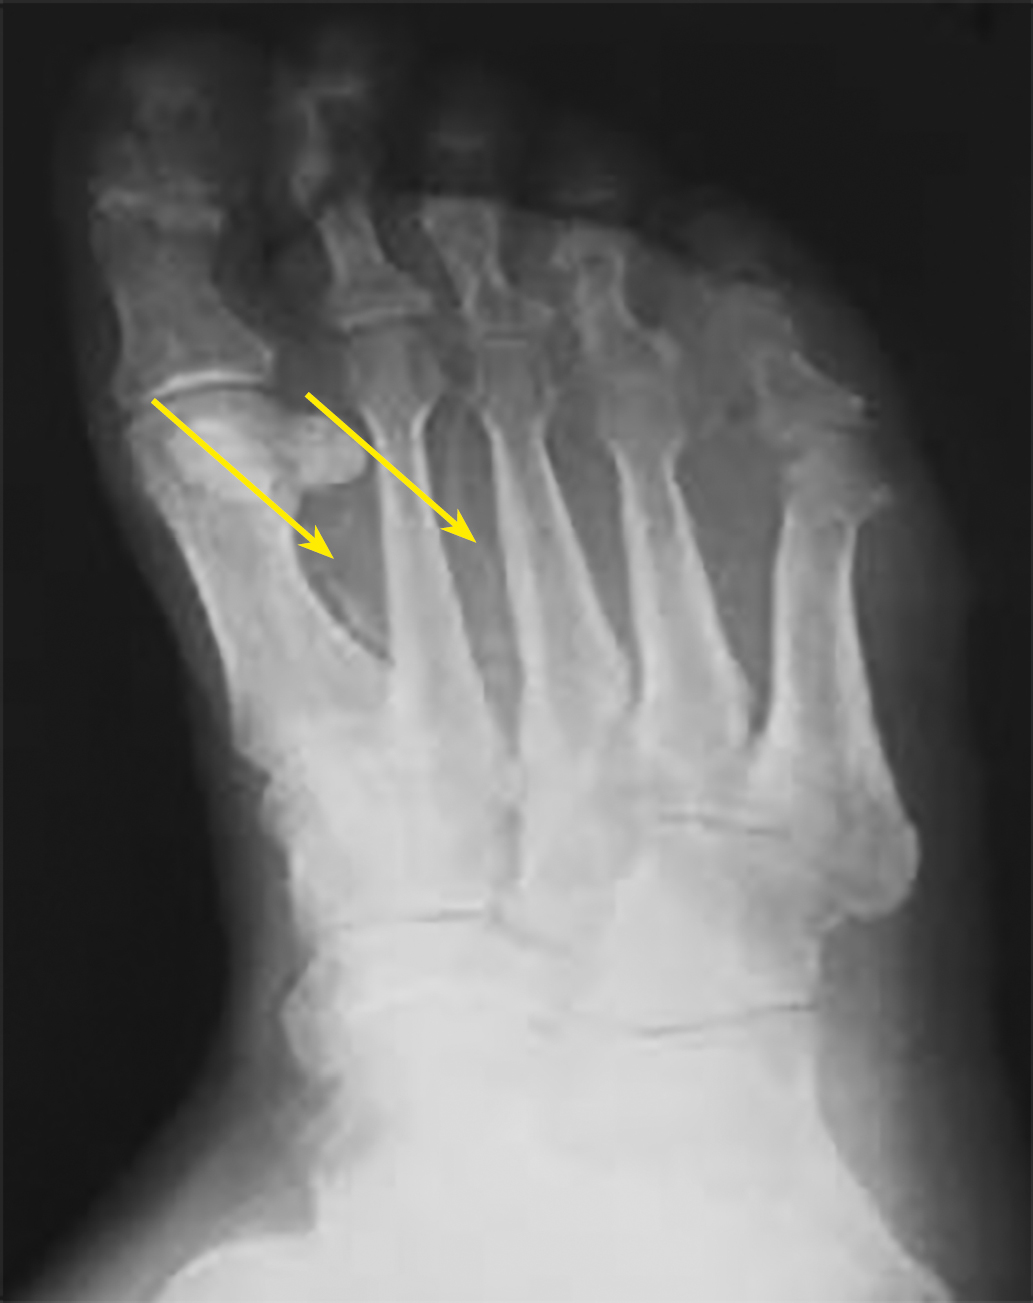

Рисунок 1. Эхограмма. В-режим. Кальциноз стенки задней большеберцовой артерии у пациента 73 лет с СД2 более 20 лет и хронической почечной недостаточностью.

Рисунок 3. Рентгенограмма стопы. Кальциноз артерий стопы (указано стрелками).